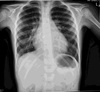

43

19.1 Paeditric cxr with history of congential heart disease repair and what was the repair based on the cxr: A) Av repair B) Pv repair C) ASD closure device D) Parachute device E) Right atrial appendage closure device

C) ASD closure device